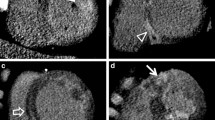

Iodinated contrast-enhanced electrocardiogram (ECG)-gated multidetector computed tomography (MDCT) four-chamber (a, c) and short-axis (b, d) views in patient 11. Upper images (a, b) show first-pass acquisition a few seconds after iodine injection. Lower images (c, d) show delayed acquisition 5 min after injection (arrowheads in c, d show subepicardial nodular enhancement). RV right ventricle; LV left ventricle

MDCT delayed acquisitions revealed myocardial late hyperenhancement in all patients. Abnormal myocardial enhancement appeared as nodular or band-like bright areas within the LV wall (Fig. 1). Abnormal myocardial enhancement was transmural in some cases and subepicardial in others but never only subendocardial. In four patients, late enhancement appeared also as thin patchy nodules within the LV wall. The mean extent of enhancement was 9±2 segments (range 7–12 segments). Late enhancement was present in the lateral wall of the LV in all patients and extended to the anterior wall or inferior wall in seven and two patients, respectively. In four patients, we observed a mild enhancement of the interventricular septum (Figs. 2 and 3). Six patients had multiple areas of enhancement scattered throughout the LV in a nonvascular, multifocal distribution.

Patient 7 with acute myocarditis predominating at an inferior and lateral location. Short axis images from multidetector computed tomography (MDCT) (a) and magnetic resonance imaging (MRI) (b) obtained close to the same level show similar subepicardial enhancement. However, the extent of subepicardial involvement in a is greater than in b, and a centromyocardial anteroseptal band of hyperenhancement is only seen in a (arrowheads). RV right ventricle; LV left ventricle